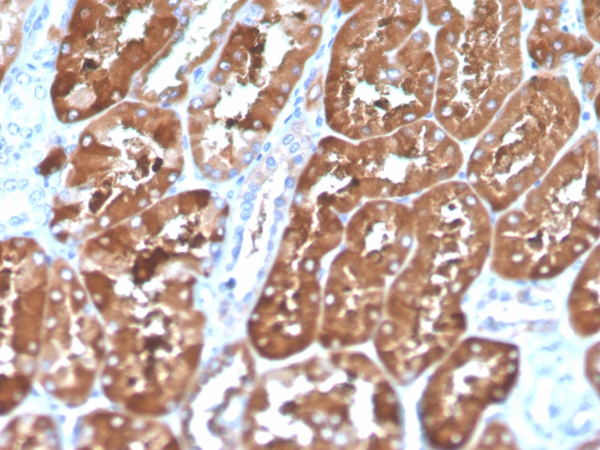

IHC (Immunohiostchemistry)

(Formalin-fixed, paraffin-embedded human kidney stained with Biotinylated Ferritin, Light Chain Mouse Monoclonal Antibody (FTL/1386).)

IHC (Immunohistochemistry)